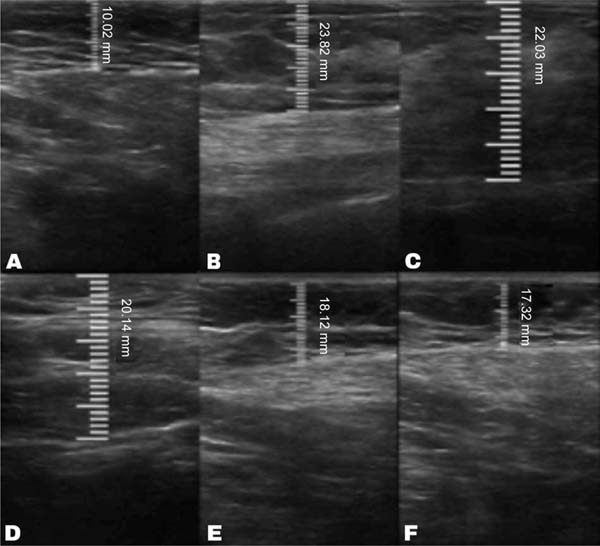

The measurement of subcutaneous tissue thickness is performed vertically, from the highest (right at the transition from the epidermis) to the lowest point (at the transition with the muscle tissue) of subcutaneous tissue thickness. This measurement is easily reproducible for those with basic ultrasound skills (►Fig. 2). In lipofilled breasts, the thickness of subcutaneous tissue was measured preoperatively and immediately after lipofilling, as well as at 15, 30, 90, and 180 days postoperatively. Measurements in millimeters were taken using ultrasound, including the vertical distance from the highest (closest to the epidermis) to the lowest point (closest to the adjacent musculature) of the subcutaneous tissue at the previously defined point. A GE LOGIQ P6 (GE HealthCare) ultrasound device with an 11L linear probe and a frequency range of 12 to 6 MHz was used, operated by a surgeon with postgraduate training in general ultrasonography (►Fig. 3).

In the decanted graft group, the average reduction compared with the initial thickness after lipofilling was 9.90% on day 15, 19.27% on month 1, 23.59% on month 3, and 26.36% on month 6. In the filtered graft group, the average reduction compared to the initial thickness after lipofilling was 7.74% on day 15, 14.85% on month 1, 20.67% on month 3, and 22.80% on month 6 (►Fig. 6). ►Figs 7–8 reveal the ultrasound change in subcutaneous tissue’s thickness before and after lipofilling. ►Figs. 9–10 show the pre-and postoperative results of one patient from each group.